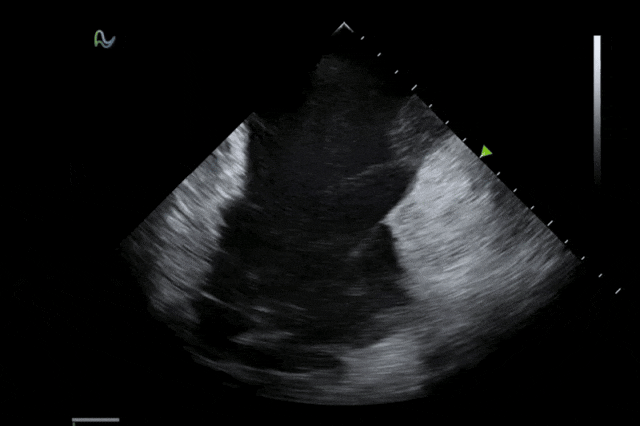

本次獲批的ICE導管在全球首次采用了80陣元大孔徑高密度探頭設計,較傳統(tǒng)普通的64陣元產(chǎn)品大幅度提升了成像分辨率、成像深度和圖像對比度,可清晰辨識心臟細微結(jié)構(gòu)和血流,為復雜手術(shù)提供更可靠的超聲成像支持。同時,8F導管憑借更小的外徑,顯著提升導管通過性和操控性,對病人創(chuàng)傷更小,尤其適合血管條件受限或小心臟患者;10F導管則憑借其優(yōu)質(zhì)的成像質(zhì)量,為復雜心臟介入手術(shù)提供精準的影像引導。